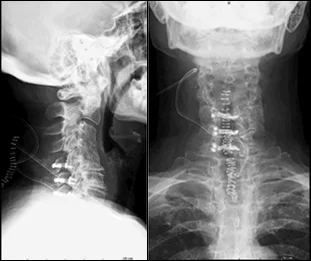

Before & After Clinical Gallery

We showcase real patient cases (with consent), including:

• Pre- and Post-operative MRIs and X-rays

• Disc Herniations, Stenosis, and Spondylolisthesis cases

• Visible improvement in alignment and decompression

Before

After